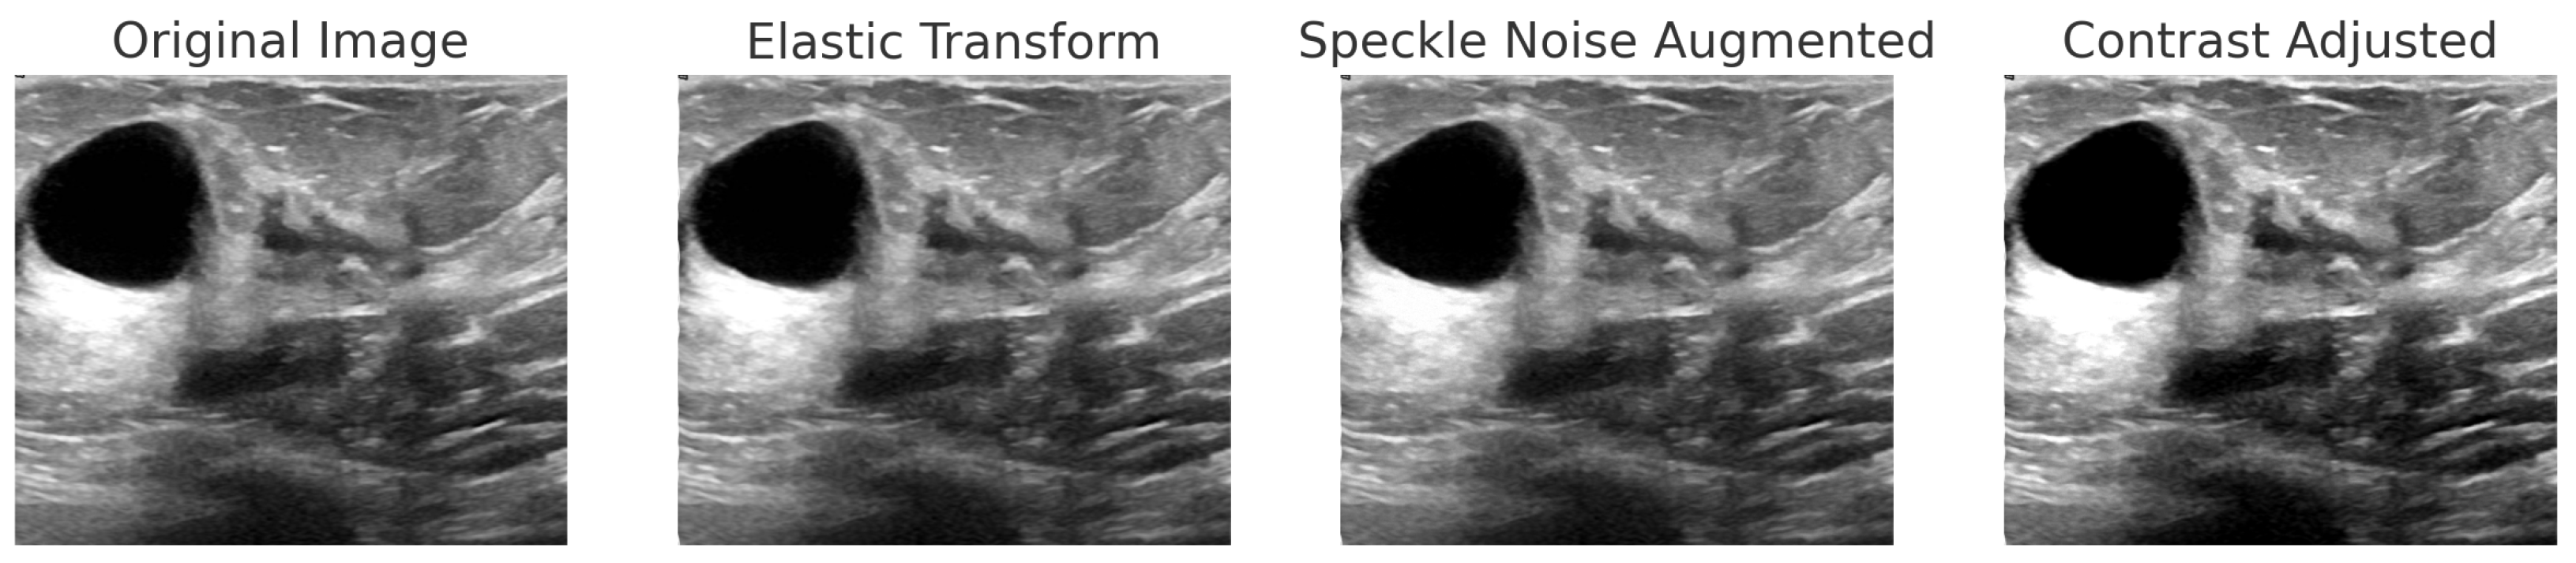

The BUSI dataset consists of 830 breast ultrasound images collected from 600 female patients aged between 25 and 75 years. These images are classified into three diagnostic categories: normal, benign, and malignant (see Figure 3). Additionally, the dataset includes ground truth segmentation masks that aid in accurate lesion delineation. Each image is saved in PNG format with a resolution of 500 × 500 pixels, ensuring consistency for preprocessing and analysis. Unlike histopathological imaging, ultrasound imaging poses challenges such as low signal-to-noise ratios and greater variability.

For BreakHis, extensive geometric (rotation ± 20°, flips) and photometric (zoom, brightness) transformations were applied to reflect slide orientation variability and staining inconsistencies. BUSI employed elastic deformation, speckle noise, and contrast adjustment to mimic tissue distortion and signal artifacts. INbreast received conservative adjustments to enhance tissue visibility without losing diagnostic fidelity. CBIS-DDSM used mild rotation, flipping, and brightness changes, maintaining lesion structure integrity. The Combined Dataset integrated harmonized augmentations from all sources, ensuring cross-modality consistency while retaining BUSI-specific elastic transformation. The chosen values prioritize generalization while preventing excessive transformations that could alter pathological features or diminish diagnostic relevance. Figure 6, Figure 7, Figure 8 and Figure 9 illustrate sample images from each dataset after the application of these data augmentation techniques.